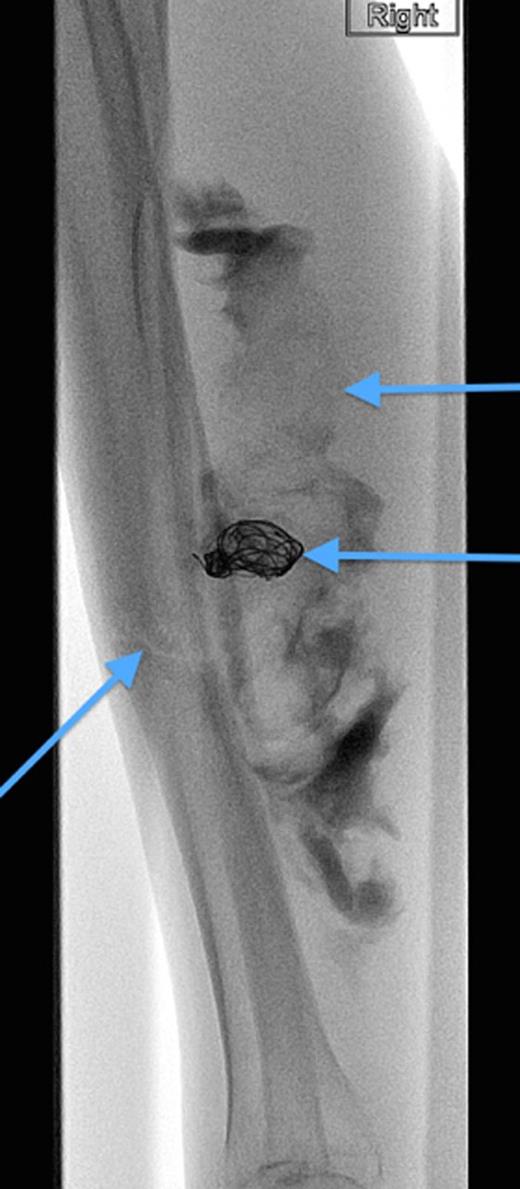

A 20-year-old man with no past medical history presented to the emergency department with non-displaced and closed transverse fracture of the left mid-tibial shaft and an intact fibula induced by a tackle during a football match. On examination, he had no neurovascular deficit and all crural pulses were palpable. His fracture was treated conservatively with a non-weight bearing above knee plaster cast later replaced by a below knee cast for a total period of 6 months. Upon examination during his attendance to the facture clinic, x-ray demonstrated no signs of fracture union. The subsequent magnetic resonance imagining (MRI) confirmed a nonunion of the fracture along with an ovoid 2.7 cm posterior compartment vascularized mass causing bowing of the interosseous septum with no evidence of avascularity of the bony margins (Fig. 1). This was confirmed to be a pseudoaneurysm originating from the PTA. An endovascular approach was adopted, and the pseudoaneurysm was injected with 2 ml of thrombin, filled with multiple coils and deployment of an angiography balloon (in the sac) (4 mm × 6 cm) for 7 min (Fig. 2). This resulted in complete cessation of the pseudoaneurysm with normal flow in the PTA (Fig. 3). The residual extravasated hematoma was later drained by an open approach. Follow-up x-ray (6 months) demonstrated complete union of the fracture site with no associated complications.

Angiographic image, demonstrating the site of the nonunion, coil insertion to the pseudoaneurysm and extravasated contrast.